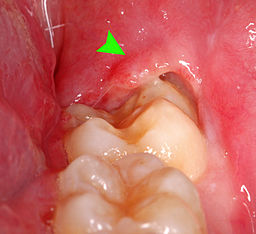

Pericoronitis is an acute infection with inflammation of surrounding safe tissues of the partially erupted impacted tooth. When the third molar (Wisdom tooth) fails to erupt completely incorrect position will pave the way for pericoronitis. But it can occur around the base of any tooth that is more common in the third molar and mostly evidenced in late adolescence (20-30yrs of age). Pericoronitis is of two types. Acute pericoronitis have severe symptoms, systemic involvement. Acute pericoronitis is seen in patients with poor oral hygiene. Chronic pericoronitis have mild symptoms and seen in patients with moderate oral hygiene. [caption id="attachment_2060" align="alignright" width="256"]pericoronitis-mage Pericoronitis-Photo[/caption]

Pericoronitis is caused by multiple facultative anaerobic bacteria which are peptostreptococcus, fusobacterium, and Bacteroides. When the tooth partially erupts it will be associated with soft tissue covering the tooth partially which is called the operculum. Third molars are located at the back of the mouth. So it makes it difficult to achieve effective cleaning while brushing. Impaction in this region will be high which becomes the favorite place for bacteria to grow and multiply. Initially the overlapped tissue (operculion) inflame if not treated infection may spread to adjacent tissues and worsen the condition. Supra erupted upper third molar can cause constant trauma to the operculum and aggravate the situation. On the inner surface of the operculum, there are various degrees of ulceration.